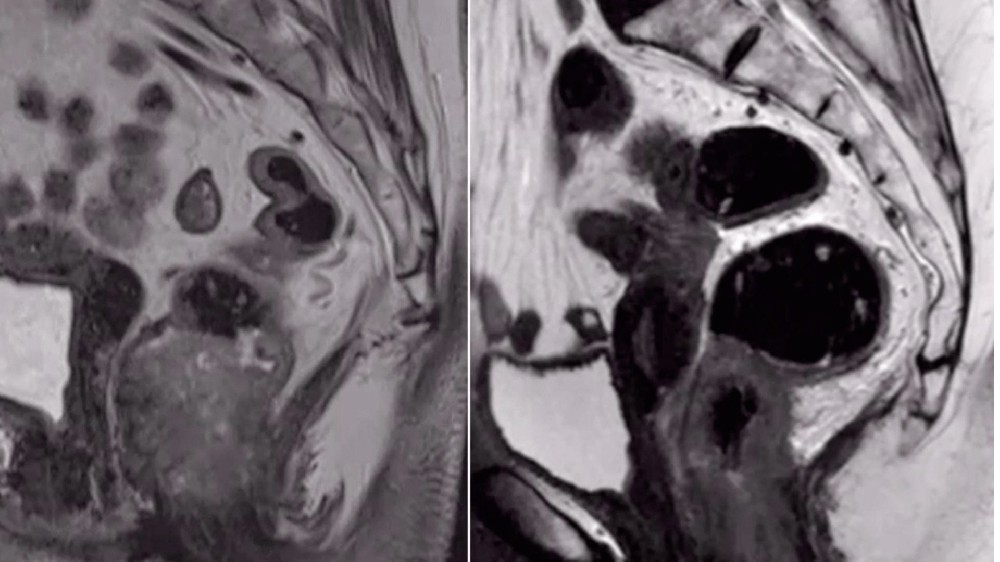

肛門癌(肛門癌)的分期和存活率

瞭解 肛門癌(肛門癌) 這對於評估疾病的進展、選擇適當的治療方法以及預測預後結果至關重要。以下,我們將根據目前的研究以及與香港和亞洲相關的區域數據,詳細介紹每個階段的常見治療方式以及相應的存活率統計。

第 1 期肛門癌(肛門癌)

在第一階段,肛門癌仍然位於肛管或肛門邊緣組織內。腫瘤通常小於 2 公分,沒有淋巴或遠端轉移:

腫瘤大小: ≤2 公分

未發現淋巴結受累或遠端轉移

治療方式包括手術切除、局部放射線治療,或結合使用以降低復發風險

在香港和較發達的亞洲地區,五年存活率普遍超過 90%

第 2 期肛門癌(肛門癌)

在第二階段,腫瘤的生長超過了最初的局部界限,但仍留在區域組織內:

腫瘤大小:通常 >2 公分,但仍在周圍結構內局部存在

淋巴結和遠端部位仍未受累(無轉移)

考慮到復發風險,通常建議結合化學放射治療

由於早期醫療介入,五年存活率仍然良好,在亞洲人口中通常介於 70-85% 之間。

第 3 期肛門癌(肛門癌)

在第 3 期和區域性癌症擴散構成突出的臨床問題:

腫瘤侵入附近的淋巴系統(骨盆或腹股溝內的區域淋巴結)

在此階段通常不會觀察到遠端轉移,但區域性擴散會使治療變得複雜

放療與化療的結合是標準的治療方式,並輔以新型靶向或代謝療法的臨床試驗,包括由諾貝爾獎得主(如 James Allison 博士)支持的潛在創新(免疫檢查點療法)。

五年存活率介於 50-70% 之間,視患者的整體健康狀況、診斷時的分期以及治療方案的反應而定。

第 4 期肛門癌(肛門癌)

第 4 期表示晚期肛門癌已從原發部位轉移到身體遠端的區域:

轉移腫瘤通常會在肺部、肝臟、骨頭或遠端淋巴系統出現

治療包括全身性治療(化療、免疫療法)、針對癌細胞新陳代謝的新陳代謝療法,以及管理整體病患症狀和生活品質的支援性或緩和性干預法。

新的治療模式正在出現,目標是將轉移性肛門癌轉變為可控制的慢性疾病,與all cancers的願景一致,即到 2025 年「將癌症轉變為可控制的糖尿病」。

在香港和亞洲的記錄中,存活率普遍顯示 3 年存活率介於 20-30% 之間,若患者能及早獲得最先進的個人化治療方式,存活率將顯著提高。